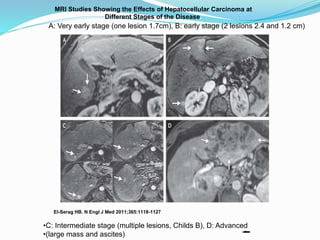

MRI Studies Showing the Effects of Hepatocellular Carcinoma at

Different Stages of the Disease.

El-Serag HB. N Engl J Med 2011;365:1118-1127

A: Very early stage (one lesion 1.7cm), B: early stage (2 lesions 2.4 and 1.2 cm)

•C: Intermediate stage (multiple lesions, Childs B), D: Advanced

•(large mass and ascites)

• #22 Figure 4 MRI Studies Showing the Effects of Hepatocellular Carcinoma at Different Stages of the Disease. All MRI studies were performed with the use of intravenous contrast material and show areas of enhancement typically found in patients with hepatocellular carcinoma. Panel A shows a single mass measuring 1.7 cm in diameter (arrows), indicating very-early-stage hepatocellular carcinoma (defined as a single lesion measuring less than 2 cm in diameter). Panel B shows two lesions, measuring 2.4 and 1.2 cm in diameter (arrows), indicating early-stage hepatocellular carcinoma (defined as fewer than three nodules, each measuring less than 3 cm in diameter). Panel C shows multiple hepatocellular-carcinoma nodules (arrows) in a patient with Child–Pugh class B cirrhosis, indicating intermediate-stage disease. Panel D shows a large mass (more than 10 cm in diameter) and ascites (arrows), indicating advanced-stage hepatocellular carcinoma.